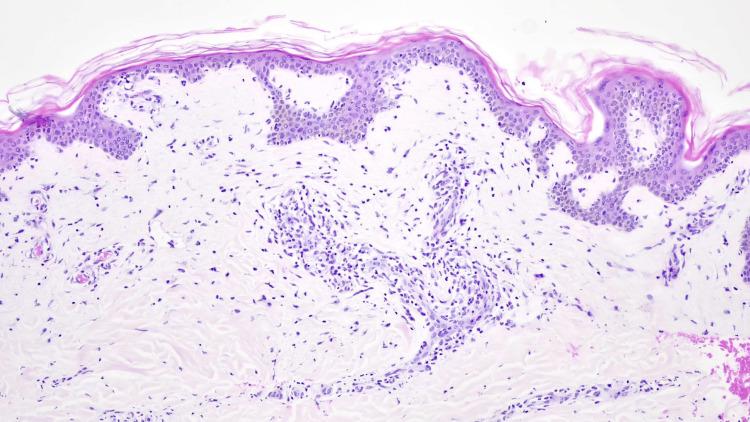

Drug reaction with eosinophilia and systemic symptoms (DRESS) syndrome is a severe, drug-induced hypersensitivity reaction characterized by widespread skin rash, multi-system involvement, and often eosinophilia. While anticonvulsants, allopurinol, and antibiotics are the most implicated agents, non-steroidal anti-inflammatory drugs (NSAIDs) such as celecoxib can be triggers in rare cases. We report the case of a 63-year-old female presenting with a 10-day history of jaundice, nausea, and right upper quadrant pain following repeated use of celecoxib. Initially diagnosed with acute hepatitis of unknown origin, she subsequently developed fever, respiratory failure, pancytopenia, and a maculopapular rash by the 20th day of hospitalization. The clinical diagnosis of DRESS syndrome was confirmed through a skin biopsy. Systemic corticosteroid therapy (methylprednisolone 0.5 mg/kg/day) led to progressive resolution of symptoms, leading to hospital discharge on day 28. This report highlights the diagnostic challenges of DRESS syndrome, particularly in the absence of eosinophilia and with rare triggers such as celecoxib.

药物超敏反应伴嗜酸性粒细胞增多和全身症状(DRESS)综合征是一种严重的药物诱导的超敏反应,其特征为广泛皮疹、多系统受累,且常伴有嗜酸性粒细胞增多。虽然抗惊厥药、别嘌醇和抗生素是最常涉及的药物,但塞来昔布等非甾体抗炎药(NSAIDs)在罕见情况下也可能引发该综合征。我们报告了一例63岁女性患者,在反复使用塞来昔布后出现黄疸、恶心和右上腹疼痛10天的病史。最初被诊断为不明原因的急性肝炎,随后在住院第20天时出现发热、呼吸衰竭、全血细胞减少和斑丘疹。通过皮肤活检确诊为DRESS综合征。全身用糖皮质激素治疗(甲泼尼龙0.5mg/kg/天)使症状逐渐缓解,患者于第28天出院。本报告强调了DRESS综合征的诊断挑战,尤其是在无嗜酸性粒细胞增多且由塞来昔布等罕见触发因素引起的情况下。